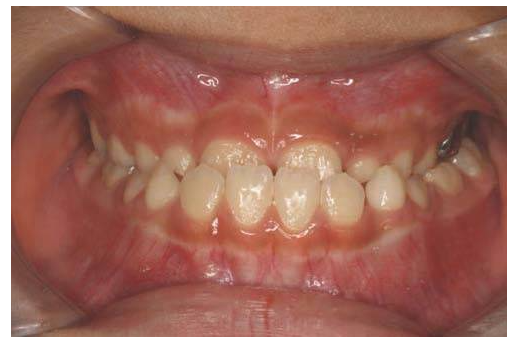

- 과개교합(Deep Bite)

위 앞니가 아래 앞니를 과도하게 덮는상태에요!

아래 치아가 거의 안보일정도로~~

이 경우 교합이 긴밀하고

잇몸에 손상을 줄 수 있어요!